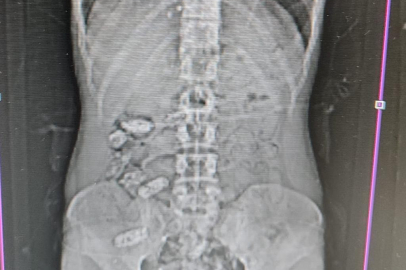

Edinilen bilgilere göre, Gümüşhane İl Emniyet Müdürlüğü’ne bağlı Narkotik Suçlarla Mücadele Şube Müdürlüğü ekipleri tarafından Akçakale Uygulama Noktası’nda durdurulan bir araç içerisindeki yabancı şahsın şüpheli hareketleri üzerine çalışma yapıldı. Uyuşturucu kuryesi olduğu ve yutma suretiyle uyuşturucu taşıdığından şüphelenilen şahsın Gümüşhane Devlet Hastanesi’nde yapılan kontrollerinde, midesinde 18 adet kapsül olduğu tespit edildi. Hastanede yapılan müdahalenin ardından şahsın midesinden çıkarılan kapsüllerin içerisinde toplamda 152,29 gram metamfetamin ele geçirildi.